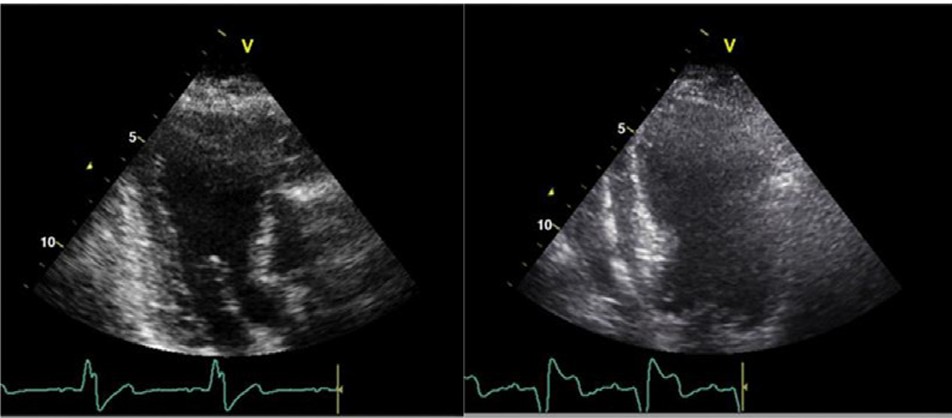

(2) Visualização limitada do miocárdio/endocárdio na sua interface com o sangue nos segmentos do ventrículo esquerdo, ou seja, a borda endocárdica precisa estar nítida em todos os segmentos. De forma geral, se mais de três segmentos estiverem tecnicamente prejudicados, o strain não deve ser considerado.